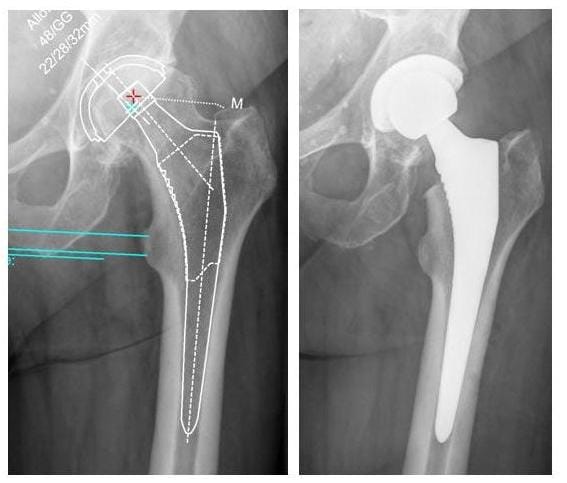

Vor dem Eingriff erfolgt eine detaillierte Operations-Planung anhand digitaler Röntgenbilder. Ein bestehender Beinlängenunterschied wird nach Möglichkeit ausgeglichen.

HÜFTPROTHESE

Bild Röntgenbild Hüftprothese

Beispiel einer zementfreien Hüftprothese:

links Planungsbild, rechts Hüftprothesenimplantation (Bilder: Orthopädie)